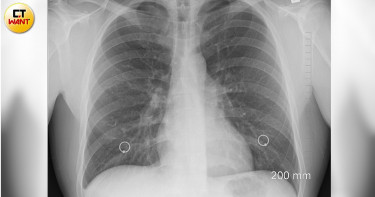

71歲張阿嬤兩年前安排「低劑量電腦斷層掃描(Low-Dose Computed Tomography,LDCT)」檢查肺部,發現一顆0.8公分肺結節,當時建議要定期追蹤,沒想到阿嬤自認「沒有不舒服」,拖到今年才回診,結果肺結節長大一倍、已增大至1.5公分。考量到結節位置適合手術處理,醫師建議進行微創肺段切除術,並在術中接受病理檢驗,冷凍切片結果確認為早期肺腺癌(第一期)。肺腺癌二期以後存活率即下降 高危險族群應定期LDCT檢查亞洲大學附屬醫院胸腔外科主治醫師劉柏毅指出,根據研究,零期或第一期肺腺癌的五年存活率接近90%,但到了第二期存活率可能下降至60%-70%,因此,早期發現與治療,對於肺癌患者的生命質量至關重要。目前健保局已針對特定高風險族群補助LDCT費用,包括50至74歲重度吸菸者、50至74歲男性/45-74歲女性,具肺癌家族史等,都可提供兩年一次LDCT。肺結節大於0.8公分 早期手術減輕病人負擔 劉柏毅說明,若肺結節大於0.8公分且呈實心狀,患者可以跟醫師討論是否採用手術切除。以目前微創手術的技術,傷口僅約3至4公分,減少患者術後疼痛和肺功能損失,且住院時間只需三至五天,恢復速度快,大幅減輕患者心理與生理負擔。此外,藉由手術切除肺腺癌,也能最大限度保留健康肺組織,對於老年患者尤其重要。肺癌也可能發生在健康無症狀族群 這樣做降低風險劉柏毅表示,阿嬤本身沒有吸菸,也沒有其他慢性疾病或家族病史,完全屬於健康無症狀族群,然而如果沒有透過LDCT檢查發現,這類小結節極難被傳統X光發現,且結節恐短期內迅速增長,一旦進入第二期或更高期別,術後可能需輔助性化療等較為積極的治療方式,並且預後效果也會受到影響。因此,劉柏毅提醒,若要預防肺癌上身,務必戒菸或減少二手菸暴露,同時定期安排健康檢查,特別是有家族病史或肺部問題的族群,應考慮定期接受LDCT。也要避免長時間暴露在空氣污染、工業排放和車輛廢氣等有害物質環境,平時也得注意均衡飲食、適當運動及良好睡眠,以提升免疫力,降低罹癌風險。

台中一名71歲阿嬤2年前就醫檢查,發現肺部有一顆0.8公分肺結節,醫師建議要定期追蹤,但阿嬤自認沒有不舒服,拖到今年才回診,沒想到肺結節長大1倍,趕緊進行微創手術切除,術後病理檢查證實為早期肺腺癌,她也才學會教訓,乖乖聽從醫師的話。亞洲大學附屬醫院胸腔外科主治醫師劉柏毅分享這起案例,阿嬤的肺結節2年前僅0.8公分,2年後增大至1.5公分,考量到結節位置適合手術處理,醫師建議進行微創肺段切除術,並在術中接受病理檢驗,冷凍切片結果確認為第一期肺腺癌。好在發現時間早,癌細胞尚未擴散,阿嬤在術後第3天就順利出院,後續檢查也顯示病情穩定。劉柏毅指出,阿嬤本身沒有吸菸,也沒其他慢性疾病或家族病史,屬於健康無症狀族群,若沒有透過「低劑量電腦斷層掃描」(LDCT)檢查發現,這類小結節很難被傳統X光發現,且結節恐短期內迅速增長,一旦進入第2期或更高期別,術後可能需輔助性化療等較為積極的治療方式,並且預後效果也會受到影響。劉柏毅提醒,肺癌是國人10大癌症死因冠軍,要預防肺癌上身,務必戒菸或減少二手菸暴露,同時定期安排健康檢查,特別是有家族病史或肺部問題的族群,應考慮定期接受低劑量電腦斷層掃描。劉柏毅強調,研究發現0期或第1期肺腺癌的5年存活率接近90%,但到了第2期存活率可能下降至60%~70%,因此早期發現與治療,對肺癌患者的生命質量至關重要。